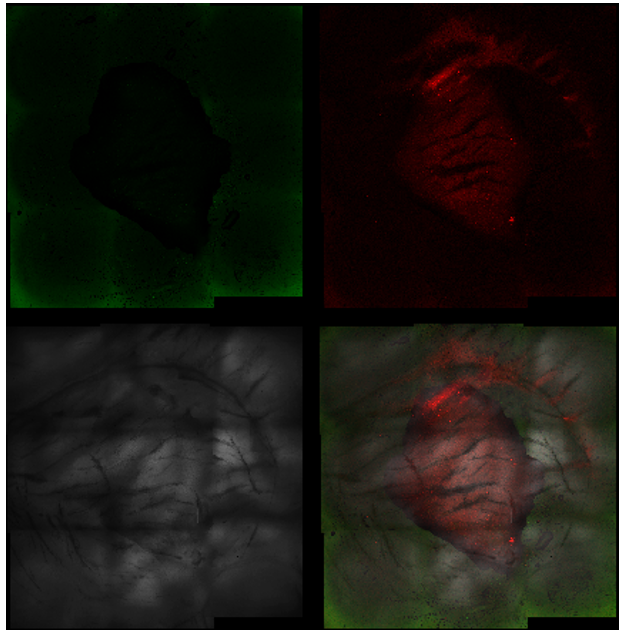

Streptococcus canis – Superficial fluorescence microscopy. Each image is divided into four quadrants: the upper left quadrant shows the green channel highlighting live bacteria; the upper right shows the red channel highlighting dead bacteria; the bottom right shows the merged green and red channels indicating live and dead bacteria; and the bottom left illustrates the bright field image. Bright green represents bacteria with intact membranes (live), red represents bacteria with compromised or dead membranes, and yellow represents bacteria with partially compromised membranes. Scale bar: 15 µm.

Pseudomonas aeruginosa – Superficial fluorescence microscopy. Microscopic imaging of Pseudomonas aeruginosa inoculated on the corneal surface and treated with UV-C for 15 seconds at a 10 mm distance. The images show clear bacterial membrane disruption and reduced viability, demonstrating the antimicrobial effectiveness of UV-C treatment on the superficial corneal layer.

Each image is divided into four quadrants: the upper left quadrant shows the green channel highlighting live bacteria; the upper right shows the red channel highlighting dead bacteria; the bottom right shows the merged green and red channels indicating live and dead bacteria; and the bottom left illustrates the bright field image. Bright green represents bacteria with intact membranes (live bacteria), red represents bacteria with compromised or dead membranes, and yellow represents bacteria with partially compromised membranes. Scale bar: 15 µm.

Panel with fluorescence microscope images of Pseudomonas aeruginosa (A & B), Streptococcus canis (C & D), Staphylococcus pseudintermedius (E & F), and a polymicrobial mix (G & H) inoculated superficially and treated with UV-C for 15 seconds.

Control samples are represented by images A, C, E, and G, and treated samples by images B, D, F, and H.

Each image is divided into four quadrants: the upper left quadrant shows the green channel highlighting live bacteria; the upper right shows the red channel highlighting dead bacteria; the bottom right shows the merged green and red channels highlighting live and dead bacteria; and the bottom left illustrates the bright field image. Bright green represents bacteria with intact membranes (live), red represents bacteria with compromised or dead membranes, and yellow represents bacteria with partially compromised membranes. Scale bar: 15 µm.

Fluorescence microscope images of the treated area with UV-C for 15 seconds (magnification 5×).

Each image is divided into four quadrants: the upper left quadrant shows the green channel highlighting live bacteria; the upper right shows the red channel highlighting dead bacteria; the bottom right shows the merged green and red channels indicating live and dead bacteria; and the bottom left illustrates the bright field image. Bright green represents bacteria with intact membranes (live bacteria), red represents bacteria with compromised or dead membranes, and yellow represents bacteria with partially compromised membranes.

It is noticeable that the central UV-C treated area contains predominantly dead bacteria, surrounded by live bacteria in the untreated area.